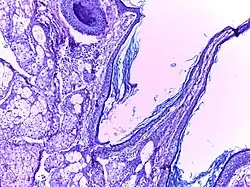

Benign cystic teratoma | Micrograph of Teratoma Ovary showing areas of cartilage, mucous glands, squamous epithelium and hair follicle. | Category: Histopathology of mature teratoma of ovary | teratoma |

![]() |